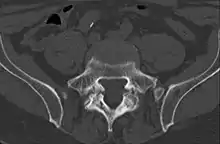

Computed tomography

Cross-sectional image of a vertebra showing spondylolysis.

Commonly known as a CT Scan or CAT scan, this form of imaging is very similar to x-ray technology but produces many more images than an x-ray does. The multiple images produce cross-sectional views not possible with an x-ray. This allows a physician or radiologist to examine the images from many more angles than an x-ray allows. For this reason the CT scan is much more accurate in detecting spondylolysis than an x-ray. Bone scintigraphy combined with CT scan is considered the gold standard which means that it is best at detecting spondylolysis.[13][15]